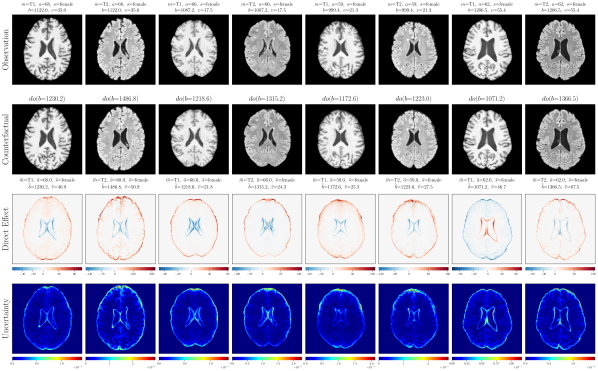

4.2 Brain Imaging Counterfactuals

To demonstrate our model’s ability to produce faithful high-fidelity counterfactuals of real data, we extend our approach to a real-world scenario involving brain MRI scans from the UK Biobank (Sudlow et al., 2015). As before, we start with an assumed causal generative process involving a set of observed variables as shown in Figure 4(a). The causal graph is medically informed and extends the scenario in Pawlowski et al. (2020) by: (i) introducing an additional MRI Sequence (T1/T2) binary variable to enable discrete counterfactuals; (ii) having directly. We used a scaled-up version of our exogenous prior HVAE as ’s mechanism and used (conditional) normalizing flows for the other mechanisms (see Appendix A.1). As shown in Figure 4, our deep SCM is capable of producing qualitatively sharp counterfactuals with localised changes according to the intervened upon parent(s) and the associated causal graph. Importantly, the identity of subjects is well preserved in all cases including null-interventions (i.e. nothing). Table 2 shows the counterfactual effectiveness results from random interventions on each variable. We observed satisfactory initial counterfactual effectiveness and significant improvements of post counterfactual training, demonstrating the merit of the proposed approach. Please refer to Appendix A.2 for notes on abduction uncertainty and D for additional results.

D.3 Extra Results

‘MRI Seq.’ counterfactuals

Post counterfactual training:

‘Sex’ counterfactuals

‘Age’ counterfactuals

‘Brain Volume’ counterfactuals

‘Ventricle Volume’ counterfactuals

Random Samples from full SCM

Null-Interventions on full SCM